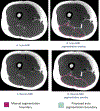

Purpose: Fast and accurate thigh muscle segmentation from MRI is important for quantitative assessment of thigh muscle morphology and composition. A novel deep learning (DL) based thigh muscle and surrounding tissues segmentation model was developed for fully automatic and reproducible cross-sectional area (CSA) and fat fraction (FF) quantification and tested in patients at 10 years after anterior cruciate ligament reconstructions.

Methods: A DL model combining UNet and DenseNet was trained and tested using manually segmented thighs from 16 patients (32 legs). Segmentation accuracy was evaluated using Dice similarity coefficients (DSC) and average symmetric surface distance (ASSD). A UNet model was trained for comparison. These segmentations were used to obtain CSA and FF quantification. Reproducibility of CSA and FF quantification was tested with scan and rescan of six healthy subjects.

Results: The proposed UNet and DenseNet had high agreement with manual segmentation (DSC >0.97, ASSD < 0.24) and improved performance compared with UNet. For hamstrings of the operated knee, the automated pipeline had largest absolute difference of 6.01% for CSA and 0.47% for FF as compared to manual segmentation. In reproducibility analysis, the average difference (absolute) in CSA quantification between scan and rescan was better for the automatic method as compared with manual segmentation (2.27% vs. 3.34%), whereas the average difference (absolute) in FF quantification were similar.